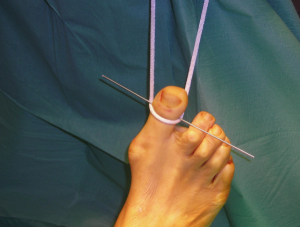

Per iniziare ….si impicca l’alluce!